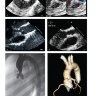

Глава 20. Врожденные пороки сердца

Глава 21. Приобретенный порок сердца

Глава 22. Аневризмы грудного отдела аорты и расслоение аорты